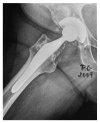

More than twenty years ago, hydroxyapatite (HA), calcium phosphate ceramics, was introduced as a coating for cementless hip prostheses. The choice of this ceramic is due to its composition being similar to organic apatite bone crystals. This ceramic is biocompatible, bioactive, and osteoconductive. These qualities facilitate the primary stability and osseointegration of implants. Our surgical experience includes the implantation of more than 4,000 cementless hydroxyapatite coated hip prostheses since 1990. The models implanted are coated with HA in the acetabulum and in the metaphyseal area of the stem. The results corresponding to survival and stability of implants were very satisfactory in the long-term. From our experience, HA-coated hip implants are a reliable alternative which can achieve long term survival, provided that certain requirements are met: good design selection, sound choice of bearing surfaces based on patient life expectancy, meticulous surgical technique, and indications based on adequate bone quality.